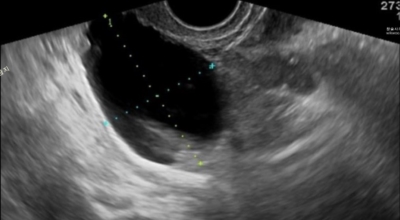

난소낭종은 이런 증상이 없는 경우가 많으며, 골반검사, 골반 초음파, 골반검사 시 터치로 확인하는 경우가 많아요. 난소 낭종이나 물집이 있는지 여부를 확인하기 위해 CT 또는 MRI와 같은 추가 검사를 수행합니다. 혈액 검사 중에 종양 마커가 상승하면 암 발생 가능성이 높아져요. 양성 질환에서도 종양 표지자가 상승하므로 세심한 분석이 필요합니다. 규모가 크지 않고 자의식이 없는 경우가 많아요.